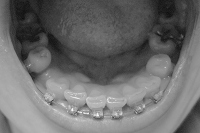

下から。

わ~い、八重歯が引っ込んだ

口を閉じてニッと笑っても唇がひっかからないから、両方の口角がすんなり上がるようになった~~。しかもちゃんと戻る~~。ってあたりまえ?

それと向かって右側の前歯の向きが少しだけ治ってます。

次回までにもうちょっと治ってくれるとよいなー。

2007/06/11撮影

2007/07/30撮影